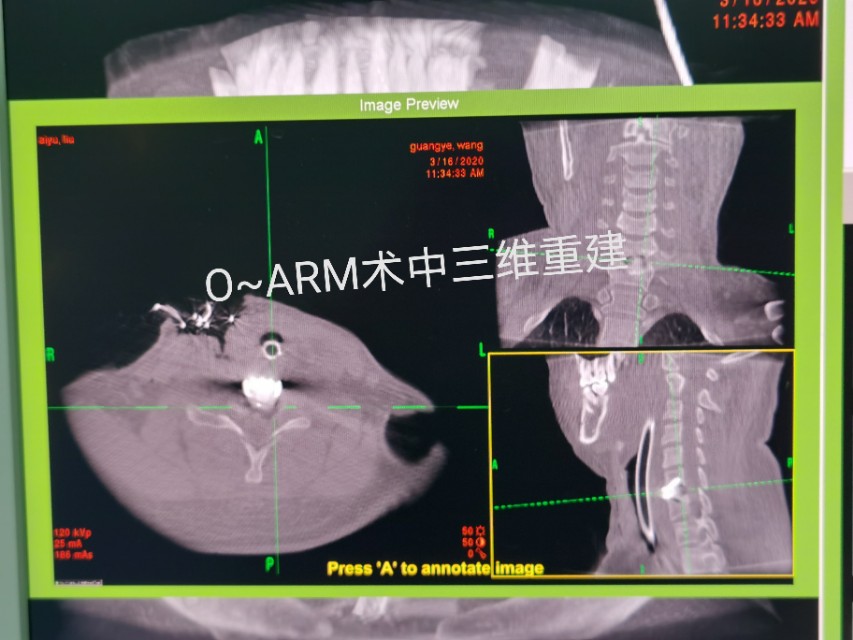

中年人疫情期居家长期卧床及长期看电脑手机,颈椎病复发今天显微镜下微创治疗,颈6-7巨大椎间盘突出.压迫神经根管,伴左上肢剧烈放射痛,显微镜下微创颈椎间盘突出治疗,用时半个小时,近零出血,取出压迫神经4块髓核,切除后纵韧带,减压至脊髓表面,脊髓恢复正常搏动,神经监护神经功能恢复好